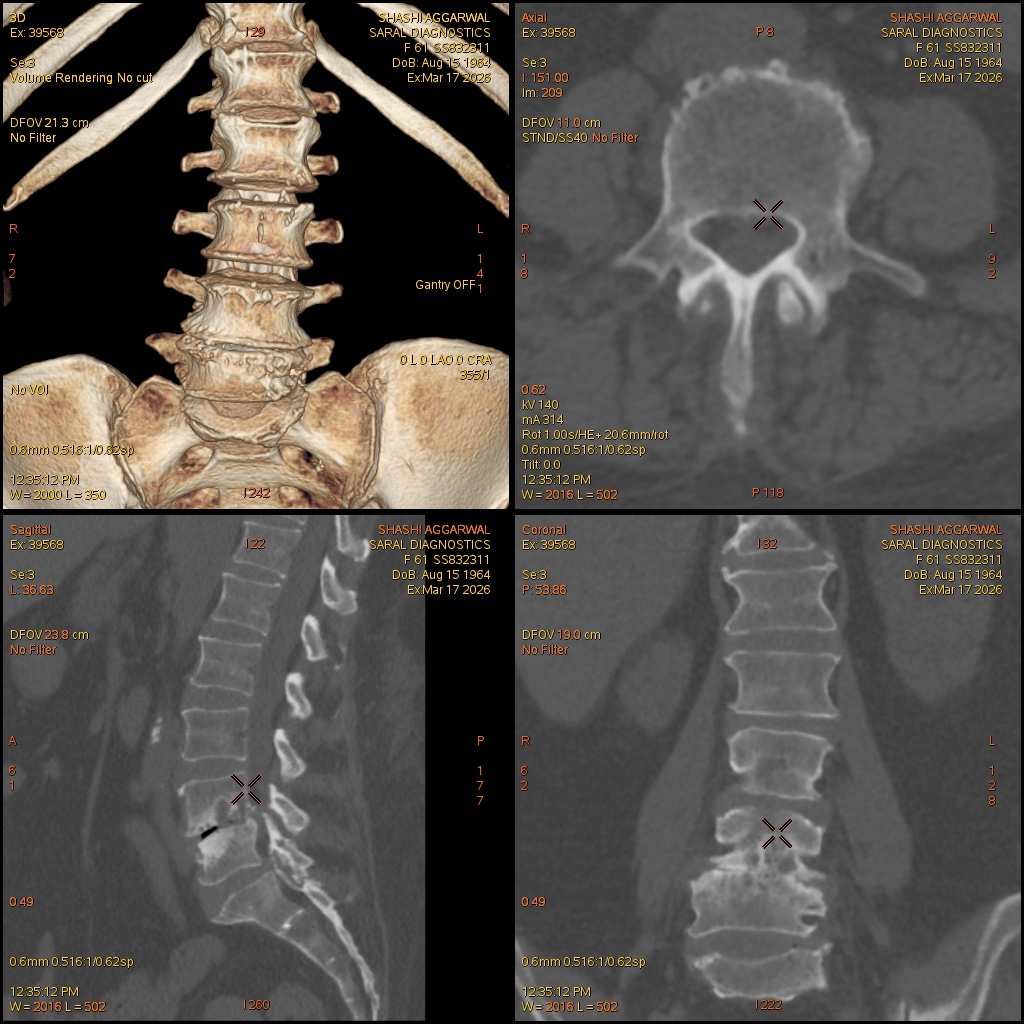

Reference Image

LS Spine (Scan charges only)